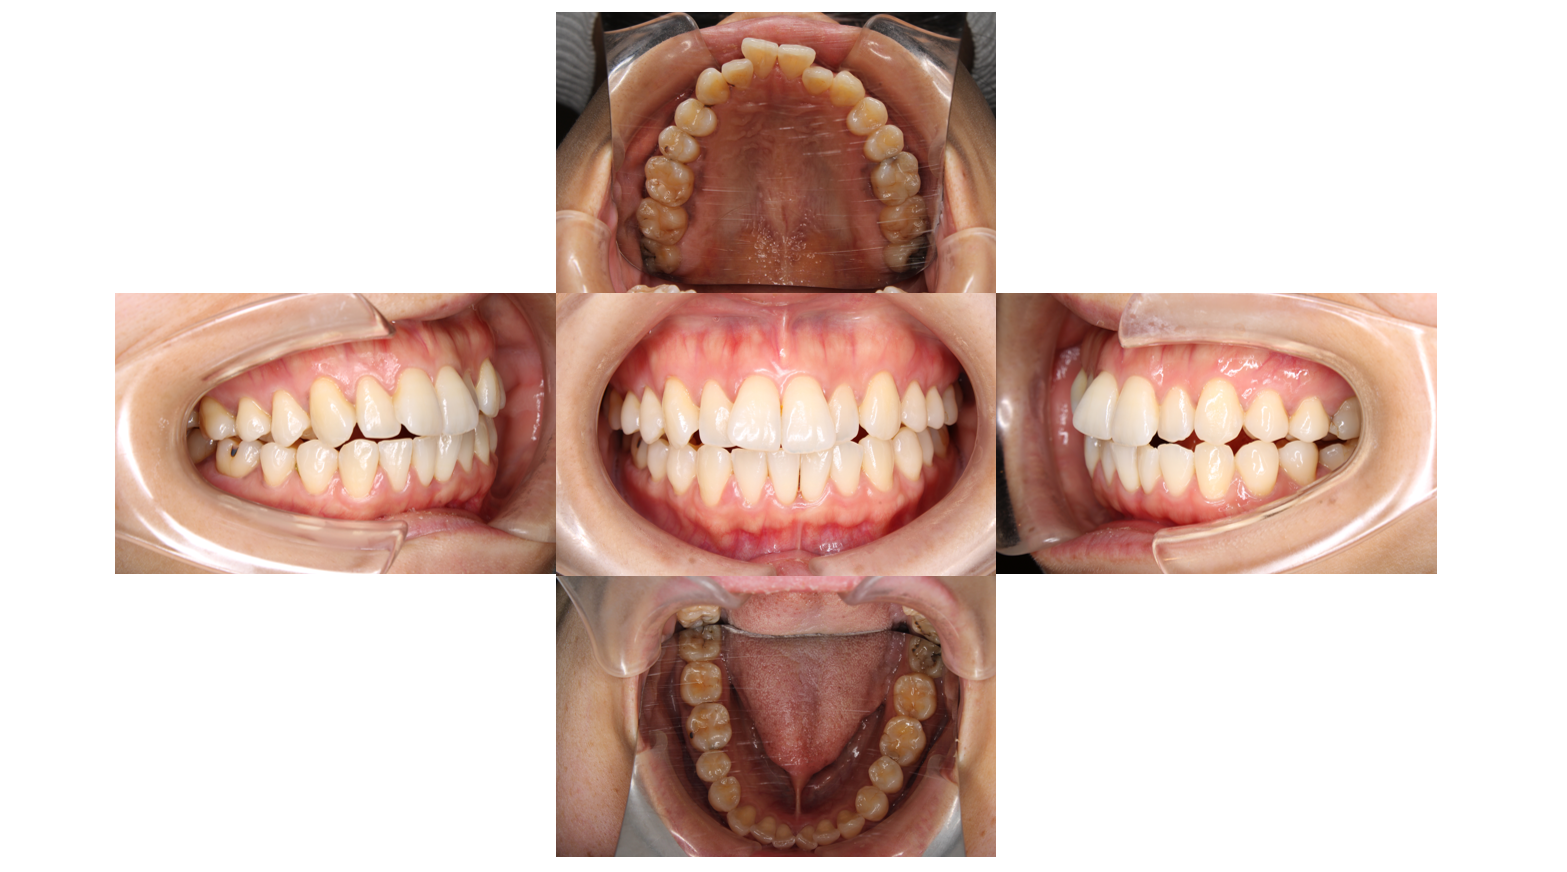

Before

主訴 | 【主訴】歯の凸凹を治したい 【診断・症状】上凸凹 |

初診